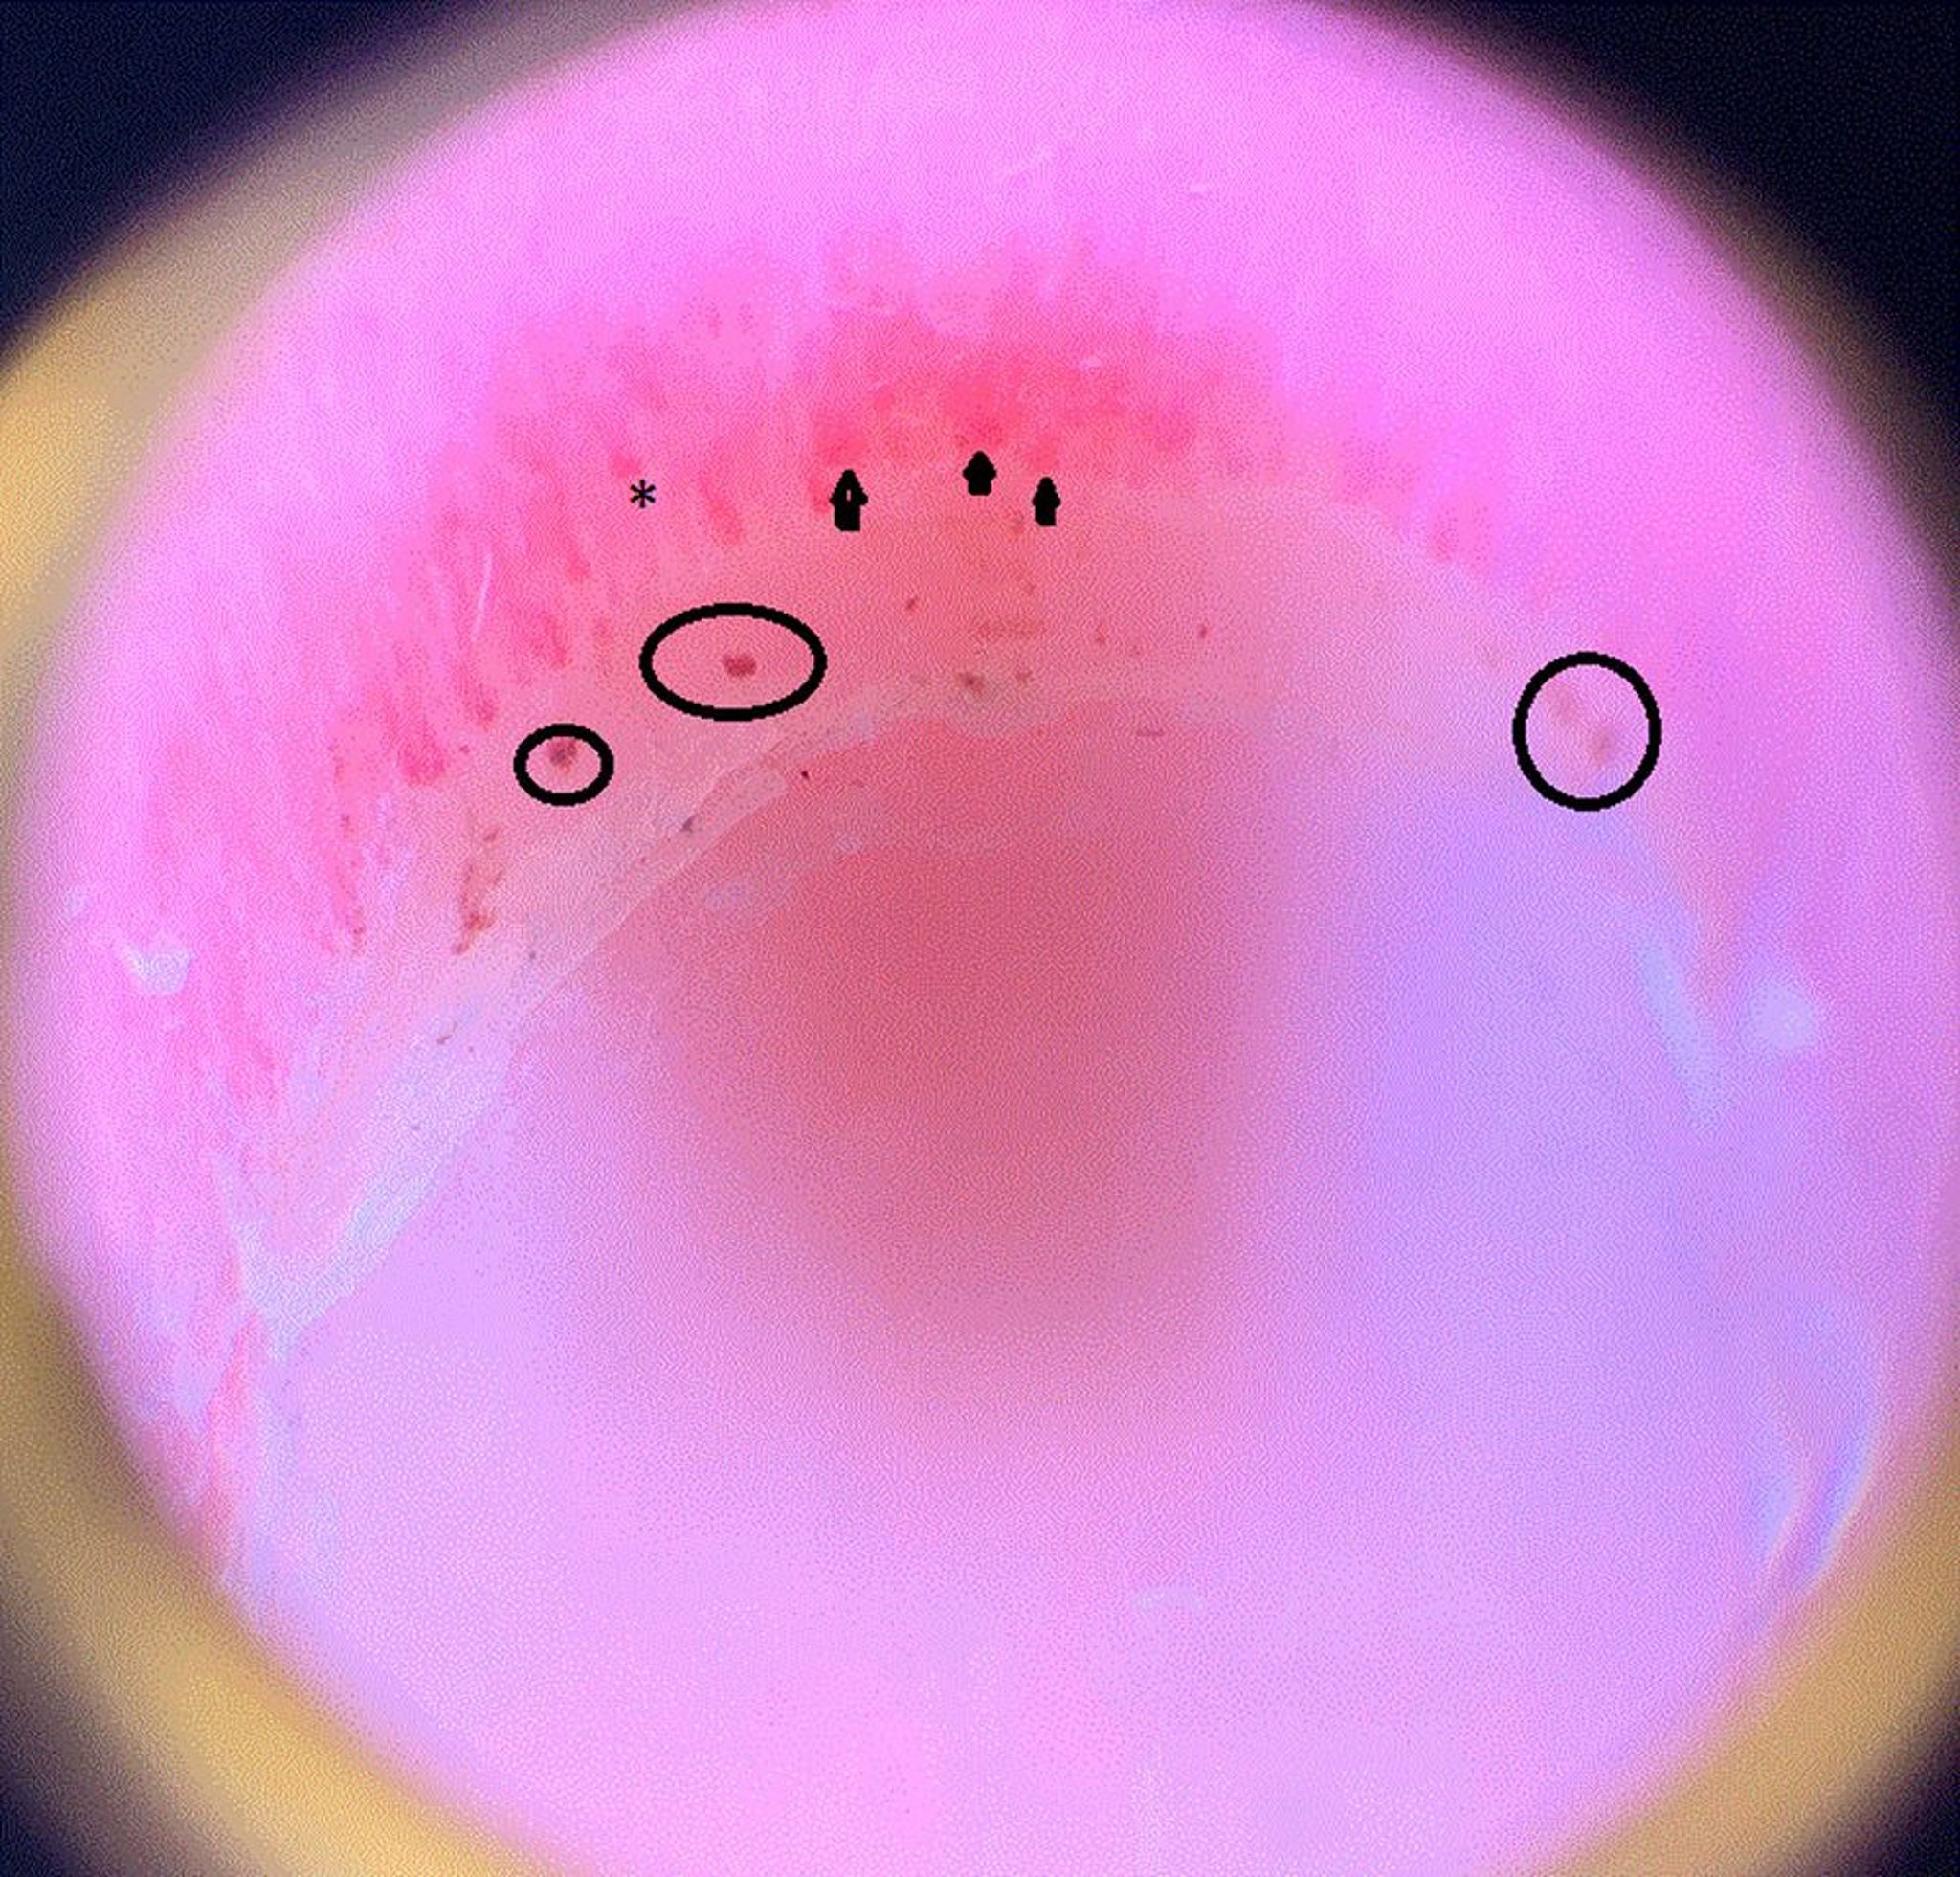

На этом изображении показаны расширенные капиллярные петли (кончики стрелок); участки выпадения, что означает, что капилляр заканчивается преждевременно и выпадает и, следовательно, выглядит короче чем другие (звездочка), и околоногтевые кровоизлияния (круги) в ногтевом ложе пациента с системным склерозом.

Image courtesy of Sanjeev Patil, MD.